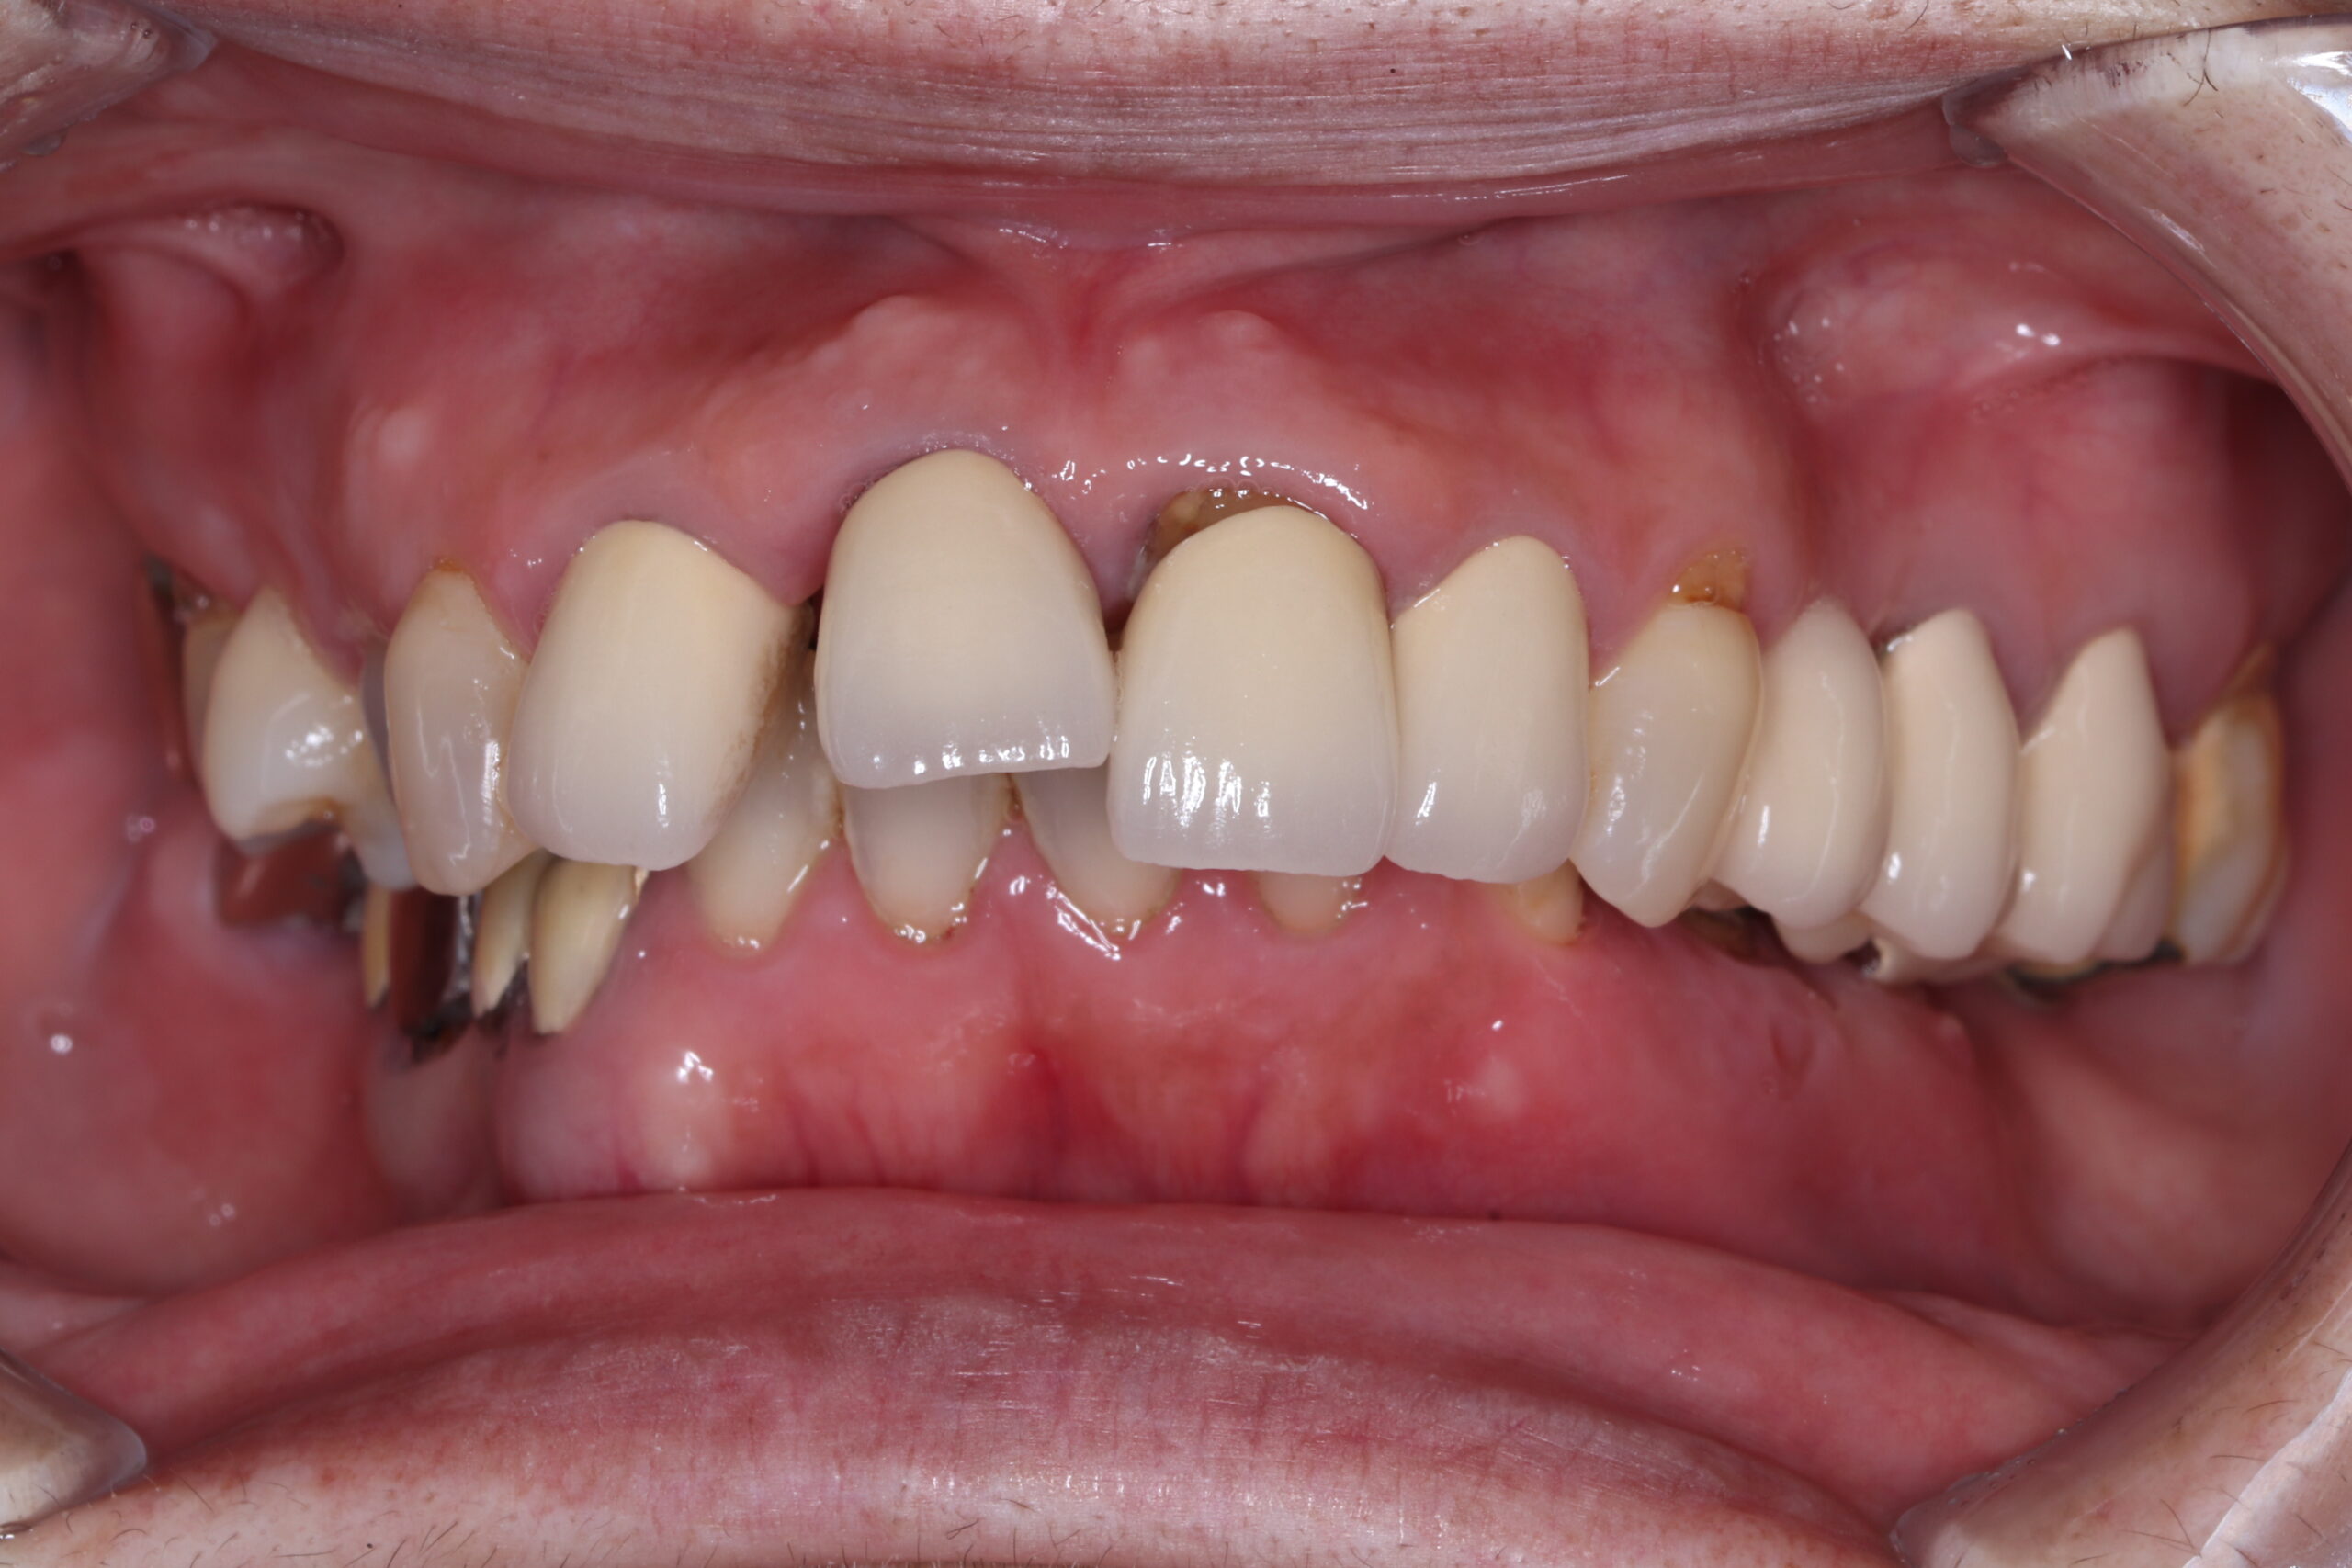

症例紹介